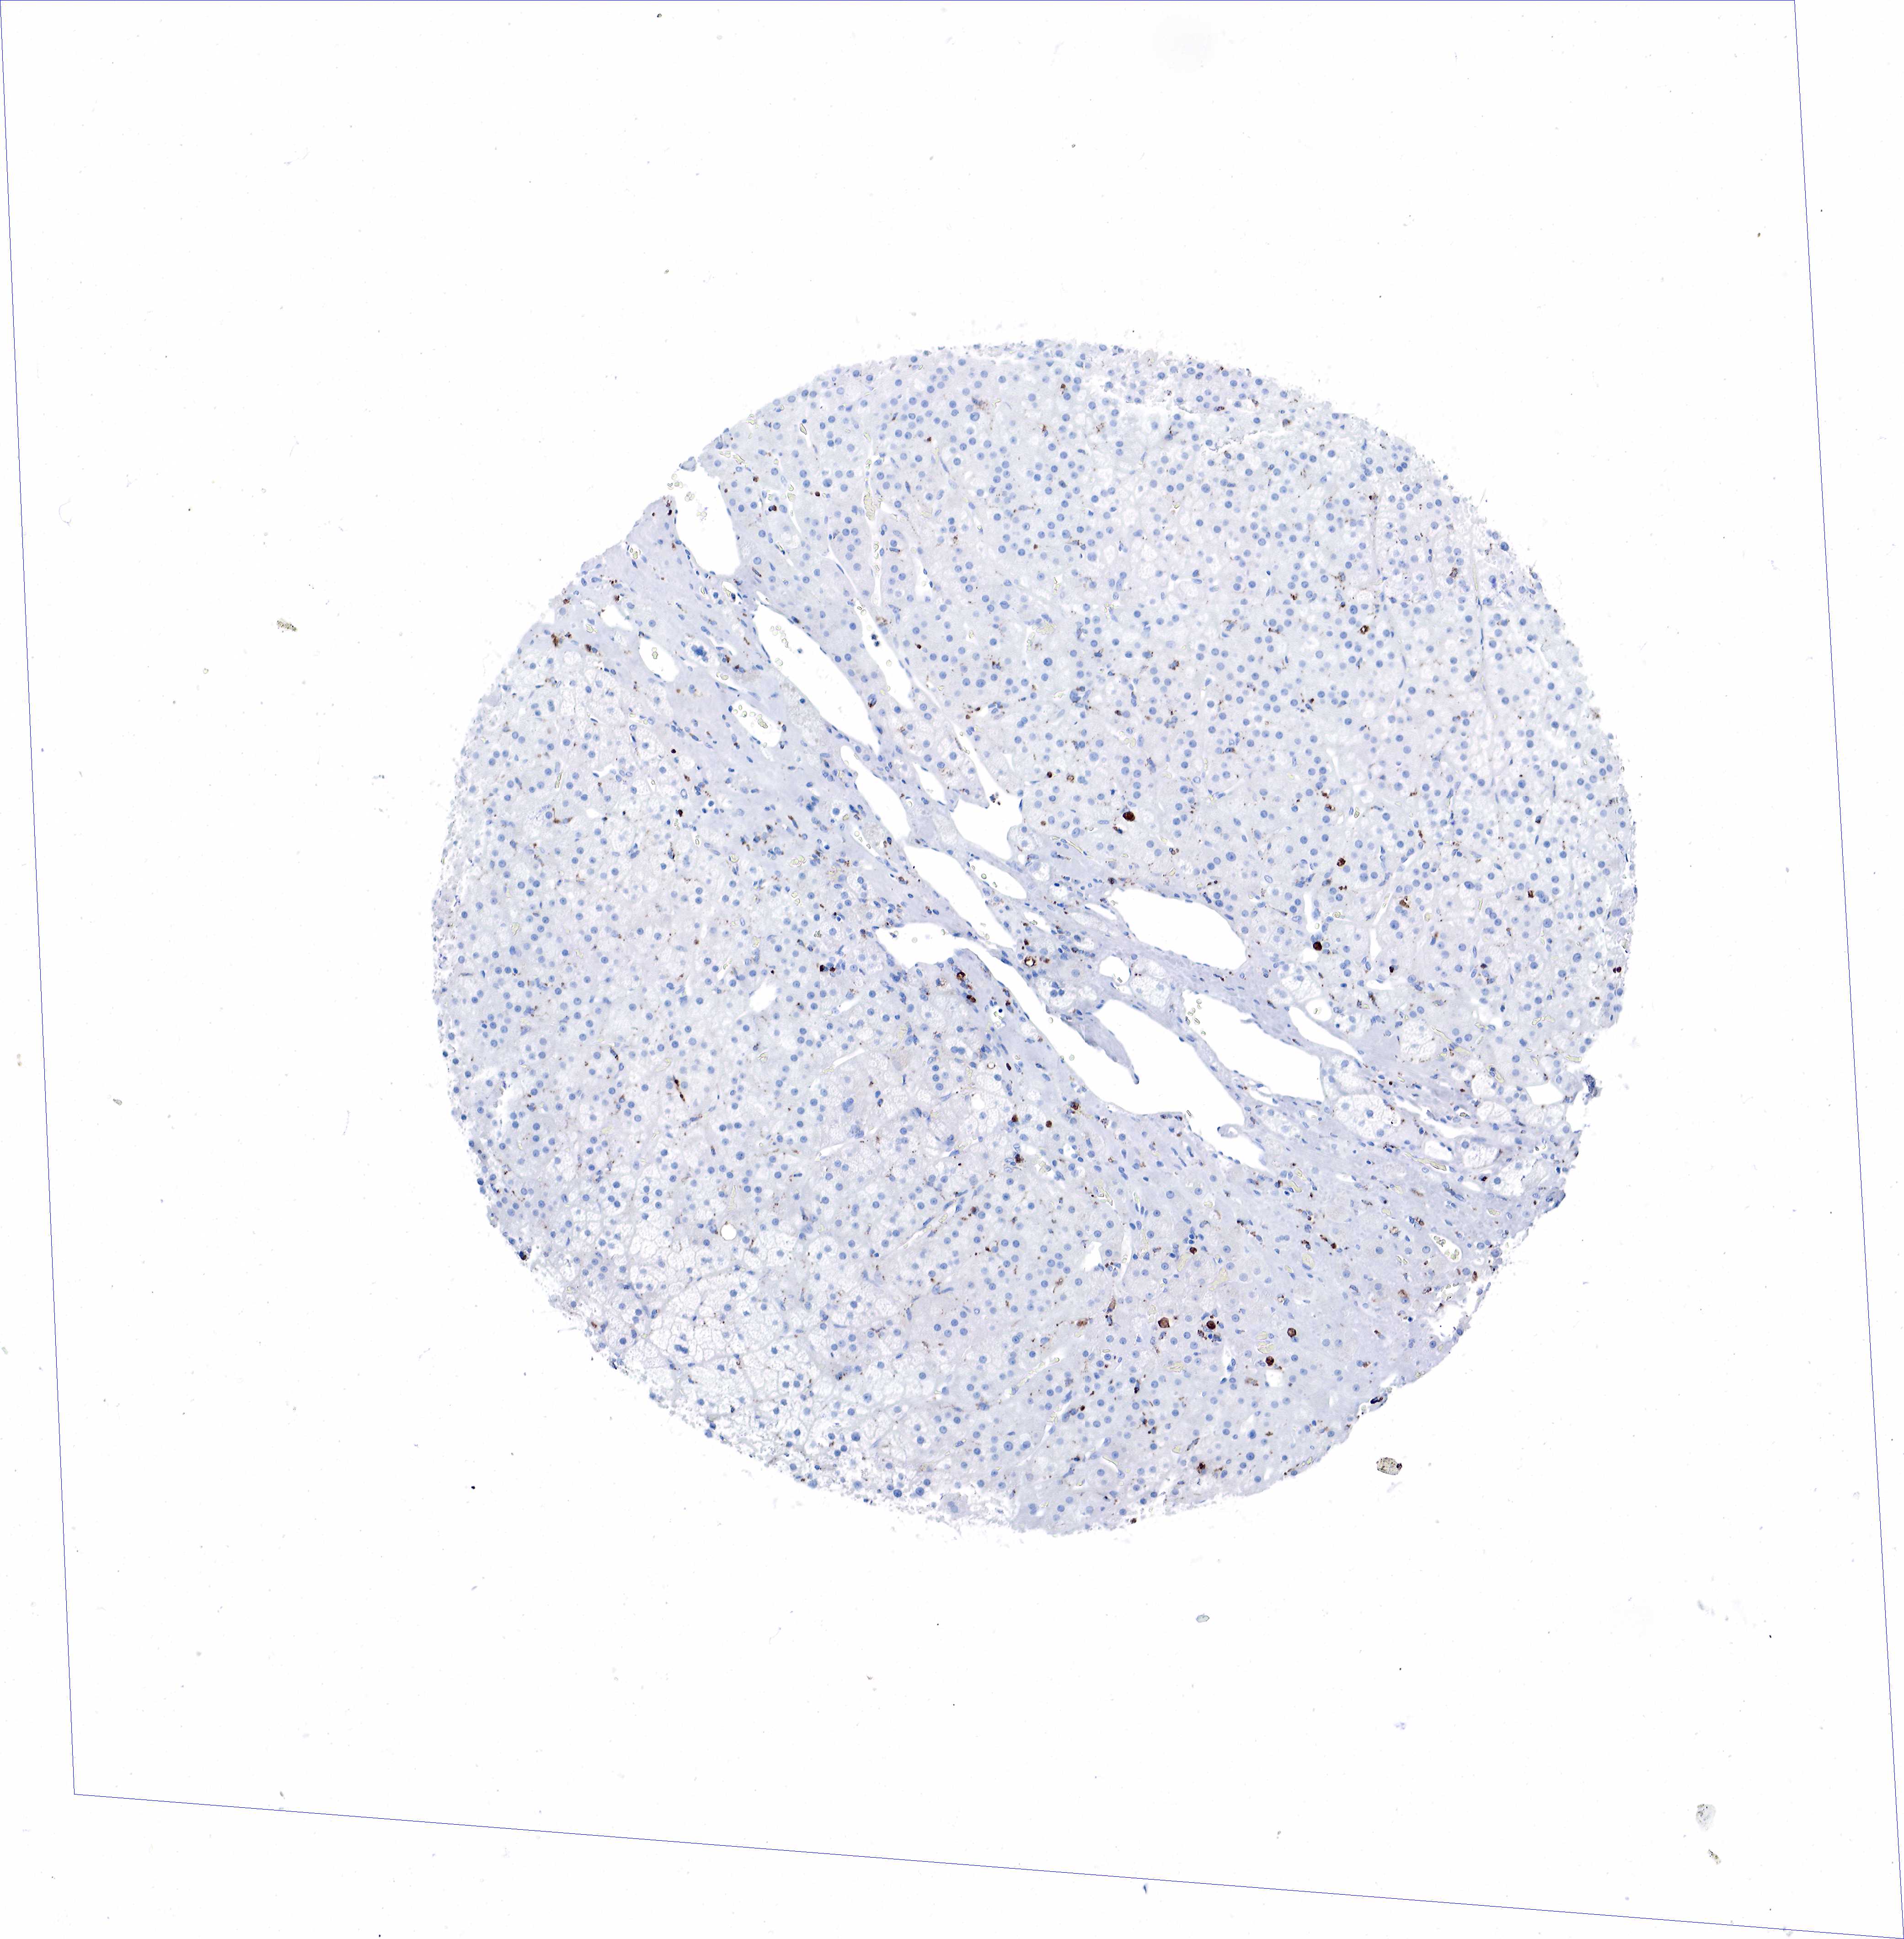

ADRENAL GLAND - Antibody stainingi

Antibody staining in the annotated cell types in the current human tissue is reported as not detected, low, medium, or high, based on conventional immunohistochemistry profiling in selected tissues. This score is based on the combination of the staining intensity and fraction of stained cells.

Each image is clickable and will lead to virtual microscopy that enables deeper exploration of all samples and also displays staining intensity scores, fraction scores and subcellular localization as well as patient and tissue information for each sample.

Antibody HPA048982Antibody CAB000051Antibody CAB000066Antibody CAB072861Antibody CAB072862

Glandular cells Not detectedNot detectedNot detectedNot detectedNot detected